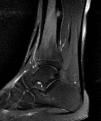

An X-ray was ordered (Fig. 1), which revealed a punctiform cortical lesion in the right tibia with a perilesional osteosclerotic reaction. Computed tomography and magnetic resonance imaging (Figs. 2 and 3) revealed an oval lytic lesion measuring 5 × 8 mm in the posteroinferior cortex of the tibia with reactive sclerosis, consistent with osteoid osteoma. In light of this suspected diagnosis, he was referred to traumatology and is awaiting treatment with radiofrequency ablation.1